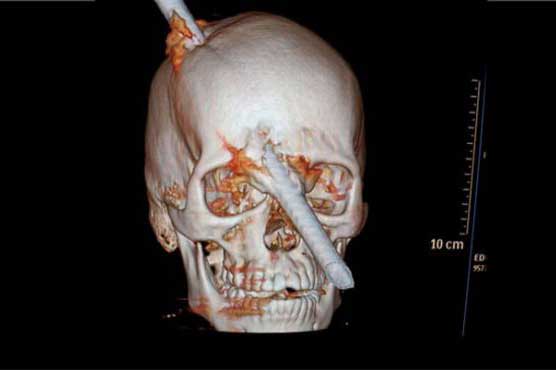

A Brazilian construction worker in Rio de Janeiro has had a miraculous escape after he was rushed to hospital with a steel pole through his brain.The six-foot (two-metre) metal rod fell from the fifth floor of a building Eduardo Leite was working on and went straight through the 24-year-olds hard hat.He was taken to Miguel Couto Hospital with one end of the rod sticking out of the top of his head and the other protruding from between his eyes.Mr Leites wife, Lilian Regina da Silva Costa, said: They told me he was laying down (in the ambulance) with the bar pointing upward.He was holding it and his face covered in blood. His look was as if nothing had happened. When he arrived he told the doctors he wasnt feeling anything, no pain, nothing. Its unbelievable.Dr Luiz Aleandre Essinger, who treated Mr Leite, said: It is a very uncommon injury this type of trauma, a steel rod that goes through the patients brain.It enters through the top of the head and goes out between the eyes. The fact that the patient arrived here lucid and talking is incredible.Doctors removed the rod during a five-hour operation and Mr Leite was able to speak, eat and move his arms and legs afterwards, the hospital said.Ruy Monteiro, the head of neurosurgery, told the Globo TV network he escaped losing his eye and becoming paralysed down the left side of his body by mere centimetres.He said the bar entered a non-eloquent area of his brain, a part that does not have a major known function.